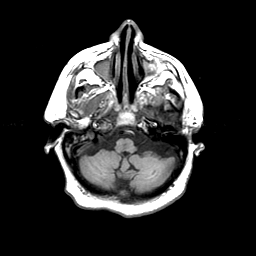

Basal Ganglia Calcification: T1-weighted MR -- Slice #3

[Home][Help][Clinical] Slice 3